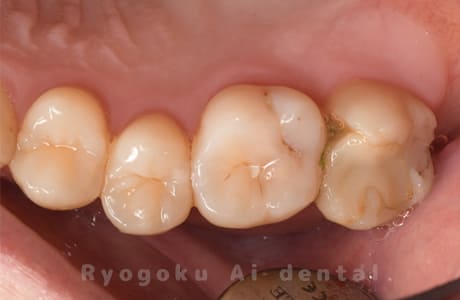

Case40

-

- 原因

- 縁下カリエス

- 治療内容

- クラウンレングスニング、ジルコニアクラウン修復

- 治療費用

- 約220,000円

被せ物の中から臭いがするとのことで、被せ物を外したところ大きな虫歯となっていました。このまま被せてしまうと被せ物が外れやすいため、埋まっている歯を出すためのクラウンレングスニング処置を行い、その後、ジルコニアクラウンで被せ物を行いました。

<リスク・副作用>

手術後は痛み、腫れ、痺れ、青あざなどの副作用が生じます。痛みは痛み止めを処方しますが、腫れ、青あざは1週間程度生じる場合があります。また、部位によっては神経の走行が複雑で、痺れが残り、長期的にお薬を処方する場合があります。